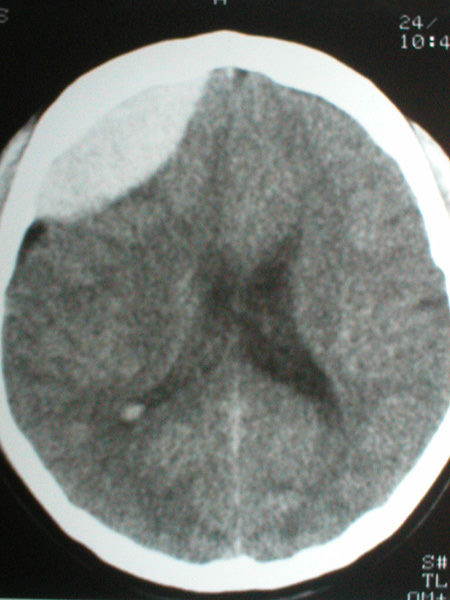

Casos Neuroloquirúrgicos

Envíado por Dr. Ruben Eduardo Amaya Contreras